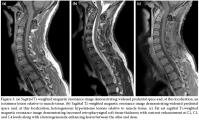

The lateral view of the cervical radiography revealed atlantoaxial subluxation (figure 1). On the computed tomography (CT), the distance between the axis and dens clearly widened as it measured approximately 10 mm (figure 2). The T1-weighted magnetic resonance imaging (MRI) showed a widened atlantodental space (figure 3a). At this localization, T2-weighted images revealed a heterogeneous hyperintense lesion, and at C2, C3, and C4 levels increased retropharyngeal soft tissue thickness appeared (figure 3b). In postcontrast T1-weighted sequences, the increased retropharyngeal soft tissue thickness and lesion showed heterogenous enhancement which was interpreted as soft tissue infection and abscess, respectively (figure 3c).